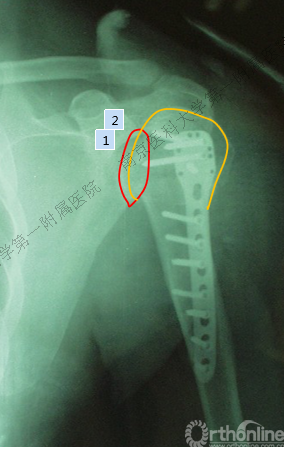

术后肩关节X线正位片

病例2

男性,48岁,坠落伤致左肩关节肿痛、活动受限1天。

Ⅲ型: +肱骨颈骨折+小结节骨折+大结节骨折(病例2),以骨折线向肱骨近端外侧壁延伸为另一特征。

五、反Hill-Sachs 损伤对肩关节稳定性的影响